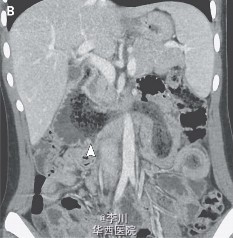

胃石症一例

主诉 病史

一位17岁的女孩因呕吐、腹痛48小时被送入急诊,该女孩患有自闭症和嗜毛癖。血常规和新陈代谢无特殊异常表现。腹部CT发现了端倪: